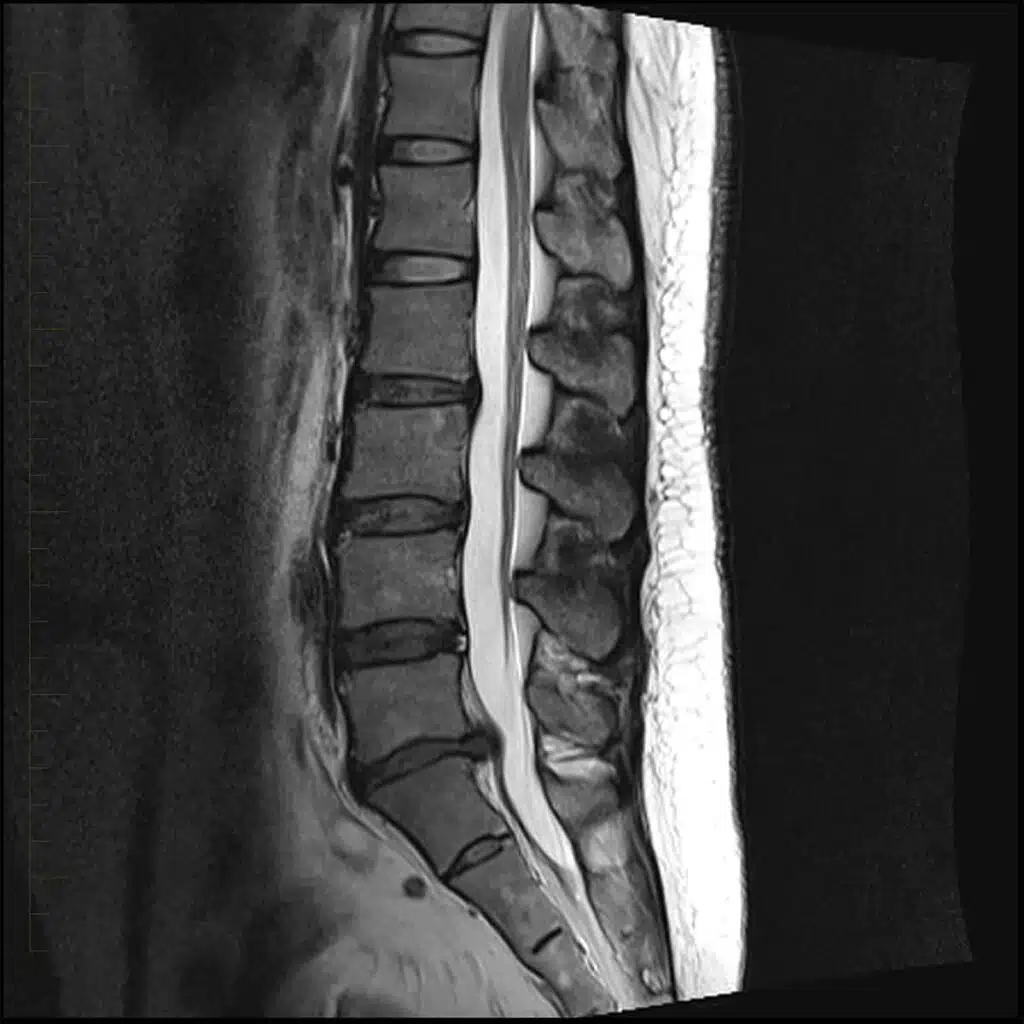

- MRI – which stands for Magnetic Resonance Imaging, uses a magnetic field and radio waves to create images of the body. MRI does a great job of visualizing tendons, ligaments, nerves, and intervertebral discs. Another benefit is that there is no radiation exposure. Unfortunately, MRI’s often are associated with longer wait times and higher cost. For more on MRIs, see How to Read a Spine MRI.